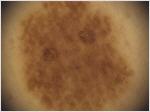

Das maligne Melanom der Haut ist bei rechtzeitiger Diagnose und Therapie beinahe zu 100% heilbar. Der wichtigste Faktor ist daher die Früherkennung und eine sofortige Behandlung. Auffällige Muttermale können neben der Inspektion und der auflichtmikroskopischen Untersuchung optional mit Hilfe der computergestützten Videodokumentation systematisch erfasst und analysiert werden. Dadurch werden exakte Verlaufskontrollen ermöglicht, die diagnostische Treffsicherheit erhöht und unötige operative Eingriffe vermieden. Die Verwendung modernster und hochleistungsfähiger Systeme ist hier unabdingbar. Ab 2018 verwenden wir noch zusätzlich das modernste verfügbare Früherkennungssystem Nevisense®, das die Diagnosesicherheit auf 97% erhöht.